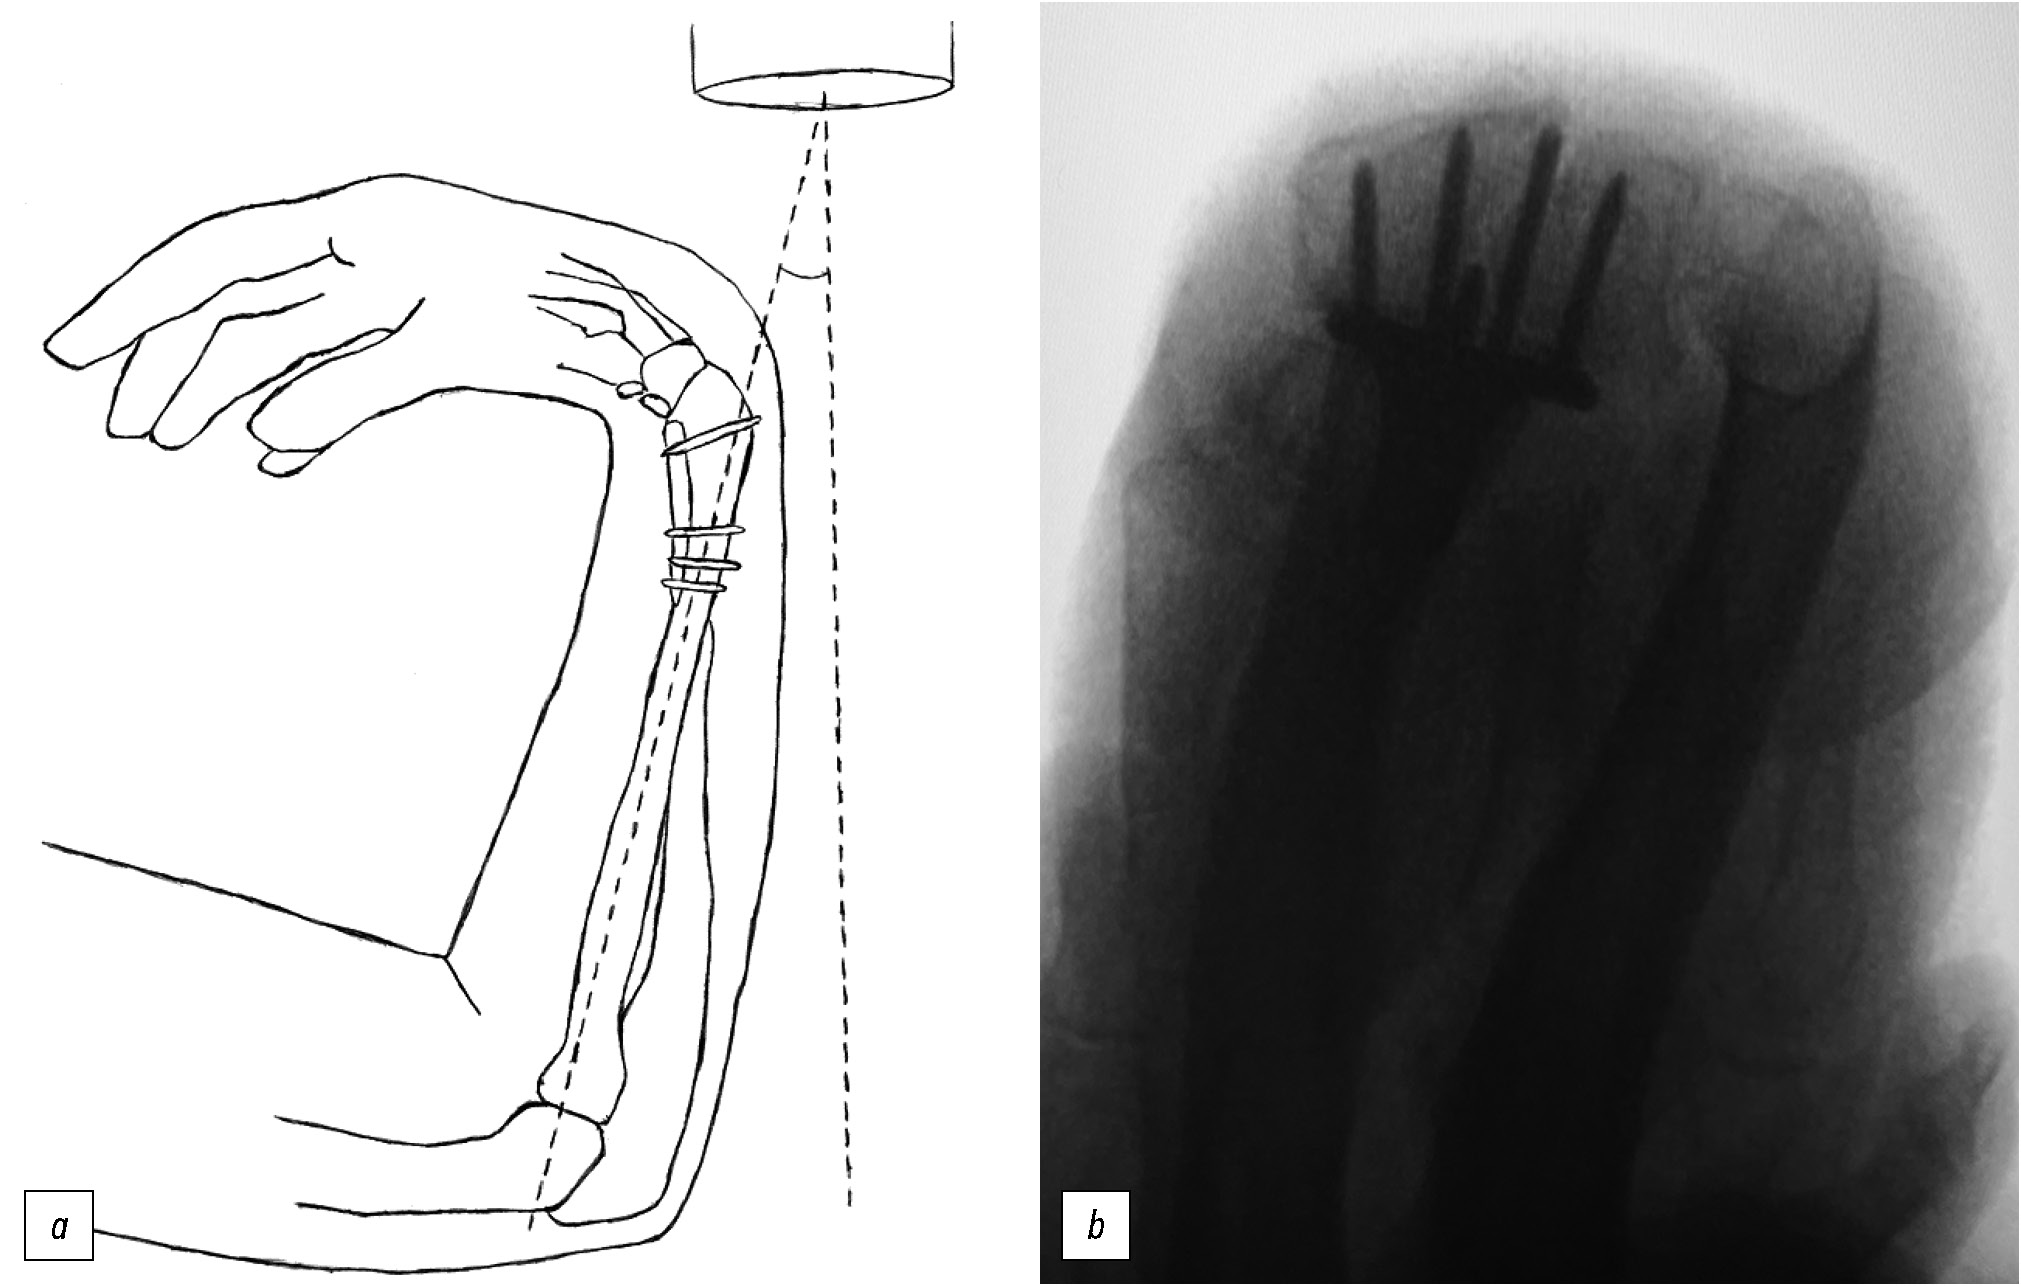

Рис. 3. Дорсальная тангенциальная проекция: a — схематическое изображение, b — изображение с электронно-оптического преобразователя.

Fig. 3. Dorsal tangential view: a — schematic representation, b — C-arm image.

К этим проекциям относятся боковая проекция с наклоном 15–30° [21, 22], косая проекция с пронацией под углом 45° [20, 23] и дорсальная тангенциальная проекция (рис. 3) [21, 24].